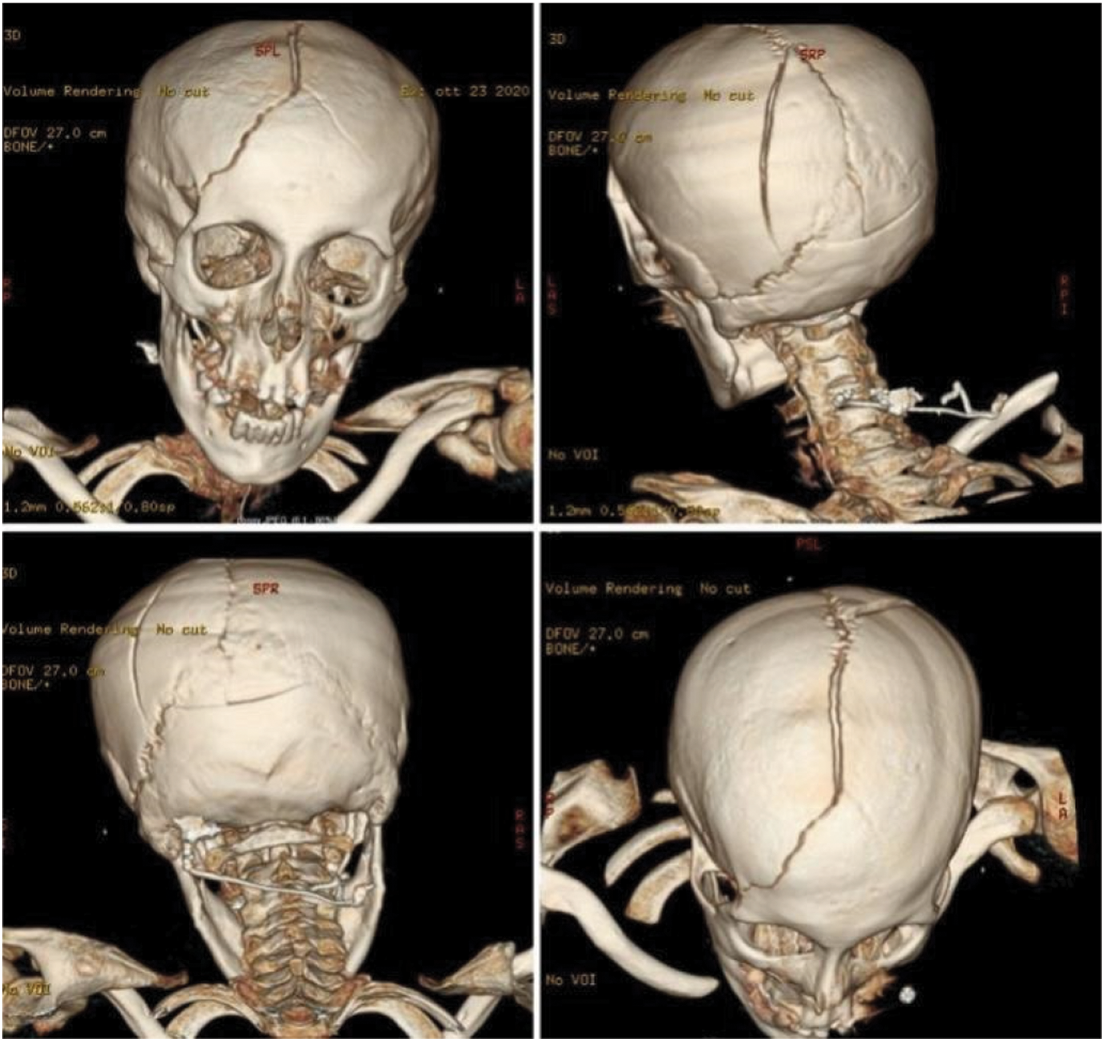

Furthermore, we found a complex skull fracture across the superior sagittal sinus, the right frontal bone, and the left parieto-occipital bones with dislocation of fragments (Fig. 3).

Figure 3: Pre-operative brain CT scan with three-dimensional reconstruction showing a complex skull fracture across the superior sagittal sinus, the right frontal bone, and the left parieto-occipital bones with dislocation of fragments